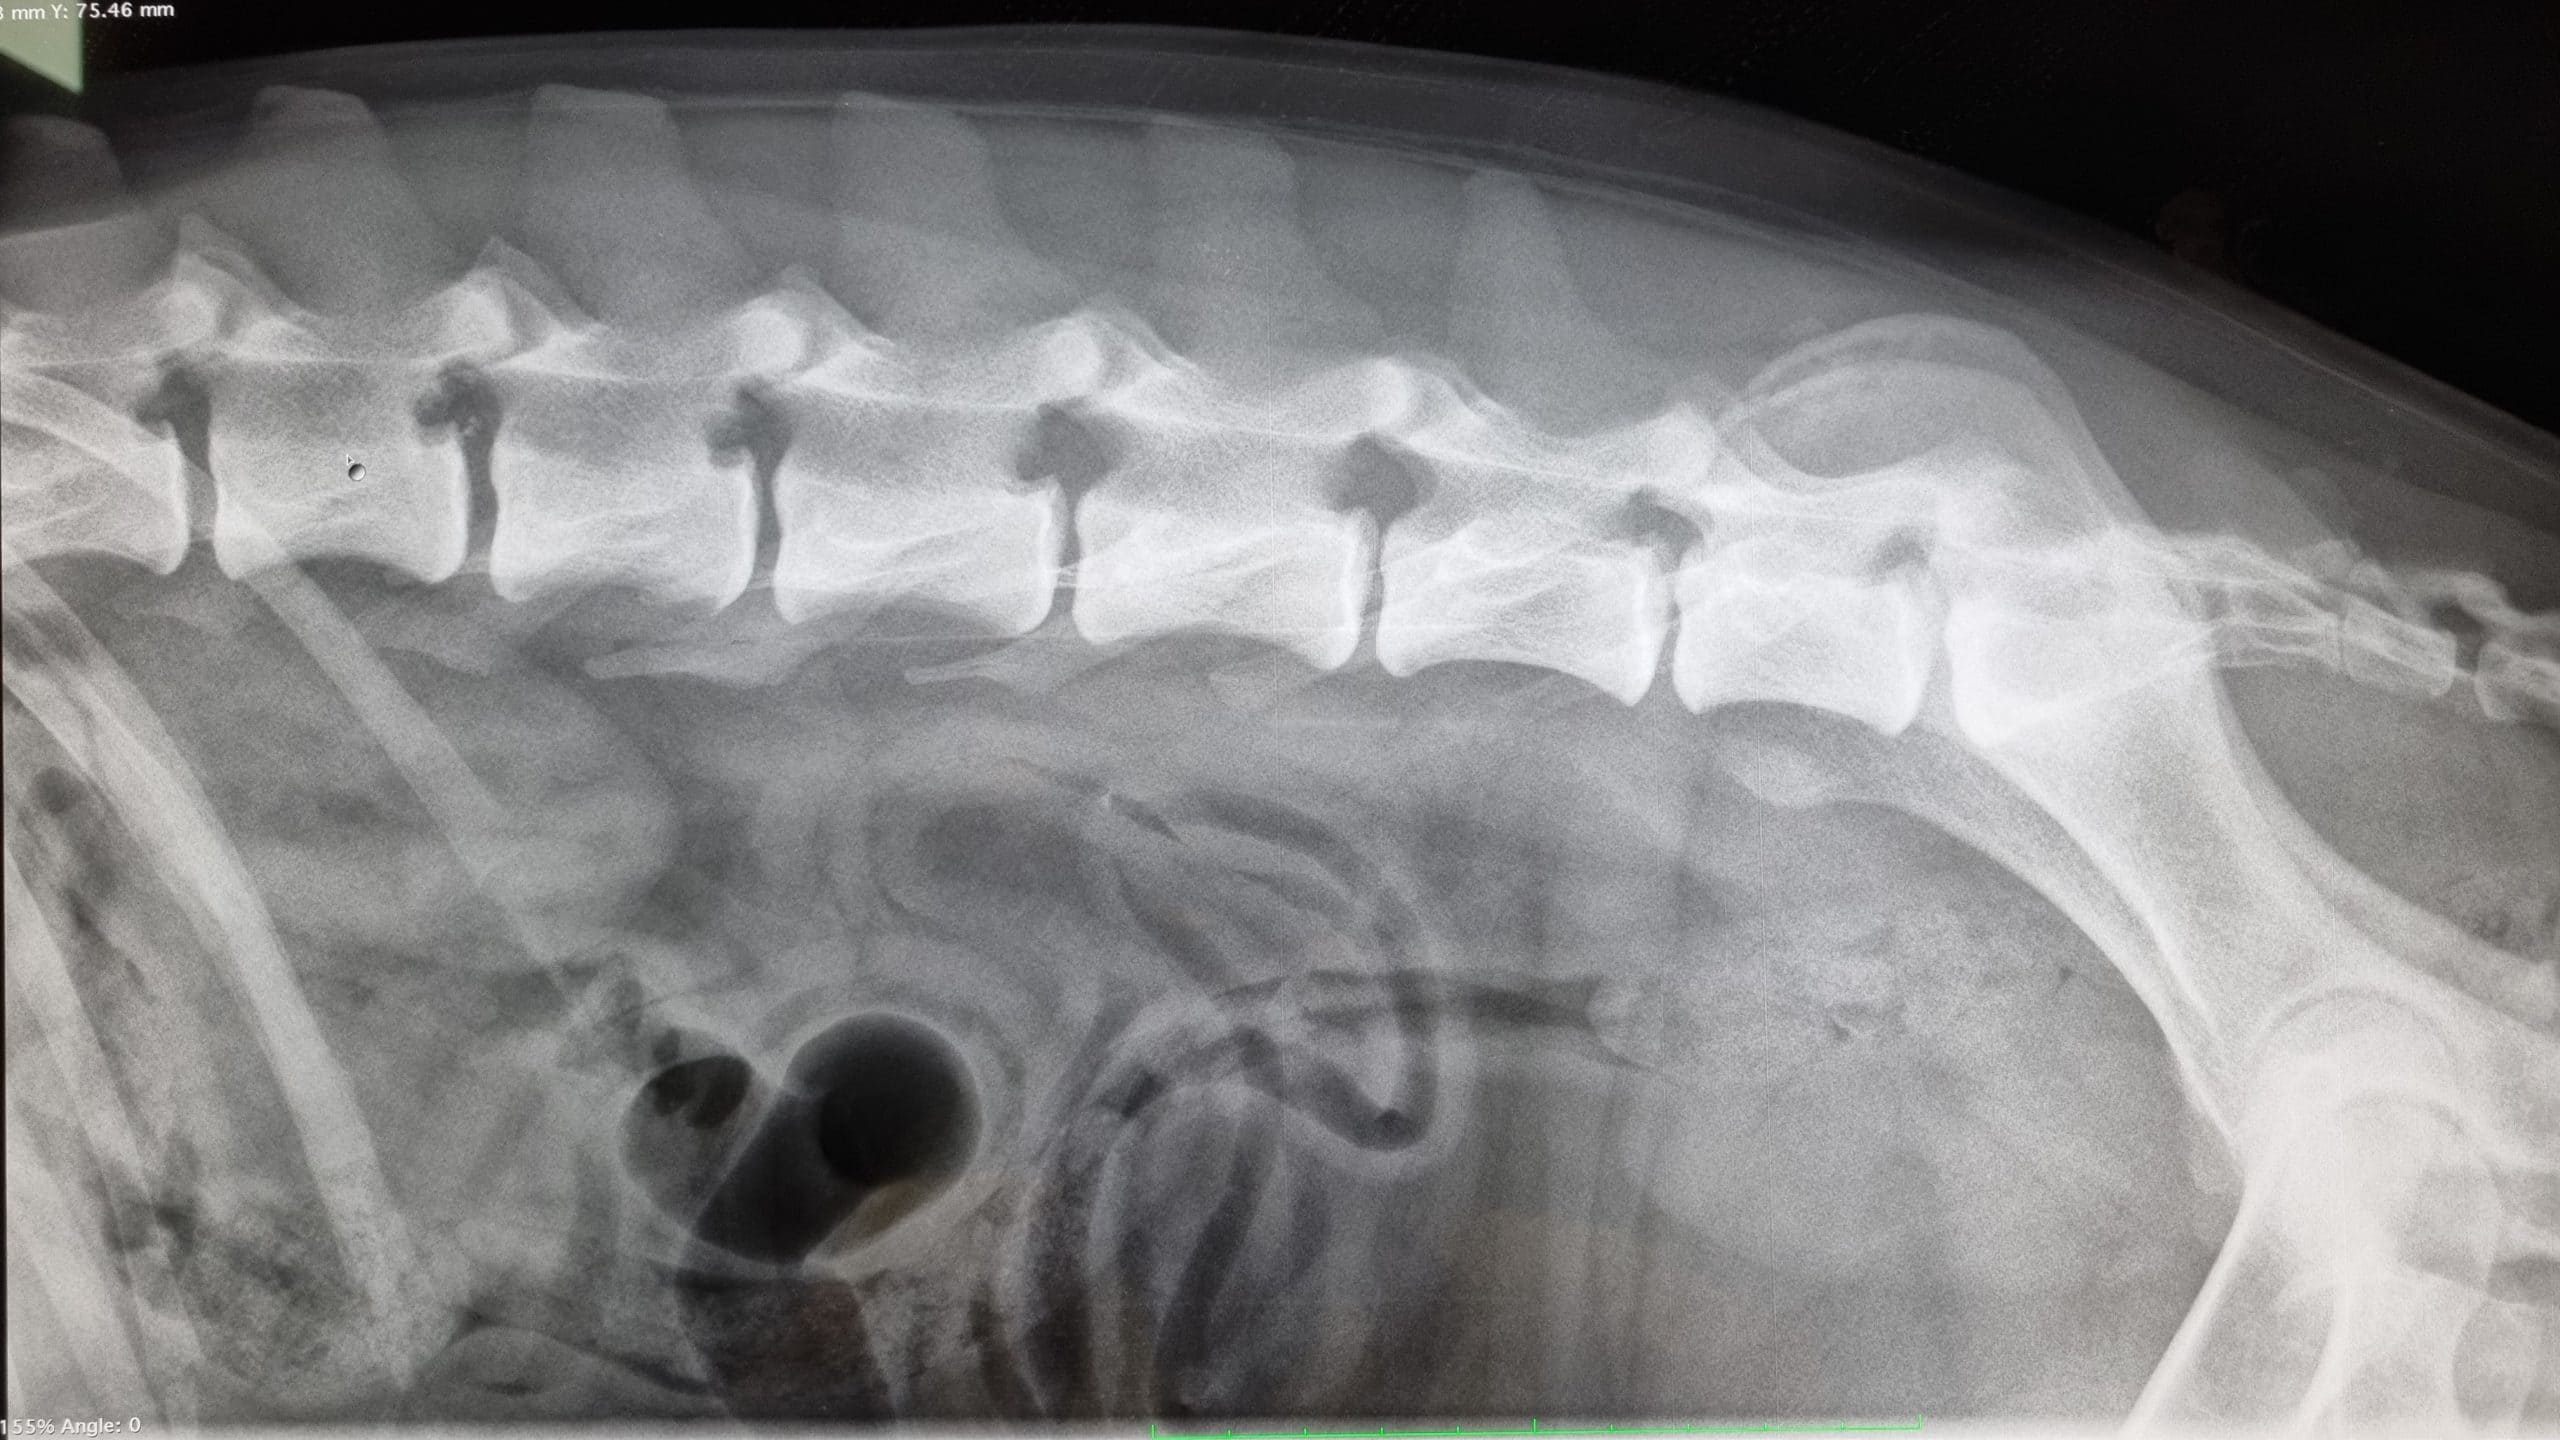

Niet iedere dierenarts mag officiële HD/ED foto’s maken of patella luxatie beoordelen. Een dierenarts mag dat alleen als hij of zij hiervoor bij de Raad van Beheer geregistreerd staat. Bij ons op de praktijk is een dierenarts aanwezig die bevoegd is om deze foto’s te maken. Als u met uw hond wil fokken kan het zijn dat er officiële röntgenfoto’s van de heupen en/of de ellebogen gemaakt moeten worden. Deze bepalingen verschillen per ras, dus neem voor de meest actuele informatie altijd contact op met de rasvereniging en/of de Raad van Beheer.

De reden dat deze officiële röntgenfoto’s gemaakt moeten worden, is dat bij een aantal rassen er erfelijke problemen aan deze gewrichten voor kunnen komen. Vandaar dat bij bepaalde rassen eerst gekeken wordt hoe de gewrichten van de ouderdieren eruit zien, voordat u mag fokken.

Voor het maken van de HD-foto is het nodig dat de hond op zijn/haar rug op de röntgentafel gelegd wordt. Sommige honden laten dit toe zonder sedatie (roesje), maar vaak moeten ze toch eerst gesedeerd worden, vooral ook omdat aan de technische kwaliteit van de HD-foto door de beoordelingscommissie (terecht) hoge eisen gesteld worden.

Sinds 1 januari 2018 hebben wij de modernste röntgenapparatuur tot onze beschikking om de problemen van uw huisdieren in beeld te brengen. In 2025 is de apparatuur weer gecontroleerd en gecertificeerd.